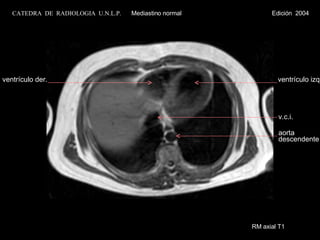

TC axial con contraste ventrículo der. aurícula izq. v. ácigos aurícula der. aorta descendente CATEDRA  DE  RADIOLOGIA  U.N.L.P.   Mediastino normal  Edición  2004 ventrículo izq. tabique interventric. pericardio

TC axial concontraste ventrículo der. aurícula izq. v. ácigos aurícula der. aorta descendente CATEDRA DE RADIOLOGIA U.N.L.P. Mediastino normal Edición 2004 ventrículo izq. tabique interventric. pericardio